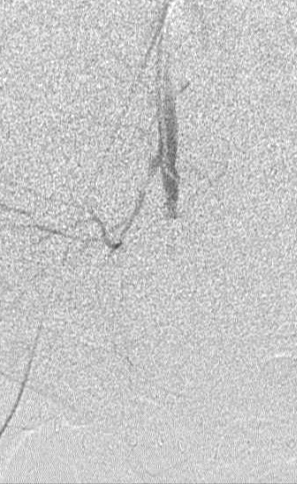

所有年龄超过 40 岁的患者, 卵巢受损 14%-43% 研究中闭经发生率(15%)与单纯UAE报告相似,可能与患者年龄(≥45岁)及卵巢储备自然下降有关。 ![]() 50岁,长期因子宫肌瘤导致月经出血过多,痛经和贫血。 子宫肌瘤栓塞术前,显示双侧子宫动脉发育不全,子宫肌瘤双侧卵巢动脉。 经皮股动脉穿刺双侧卵巢动脉栓塞,先500μm-700μm emboSphere 微球 术后4周,和6月的中短期随访,月经正常,子宫容积减少,贫血纠正,无卵巢功能衰竭。但看起来非灌注容积较少。 术后9月,由于子宫肌瘤持续存在,患者自己希望绝经,行全子宫和双侧卵巢切除术 术后病理,子宫内可见栓塞微粒伴有坏死,卵巢内也见栓塞微粒,但卵巢功能未受损。